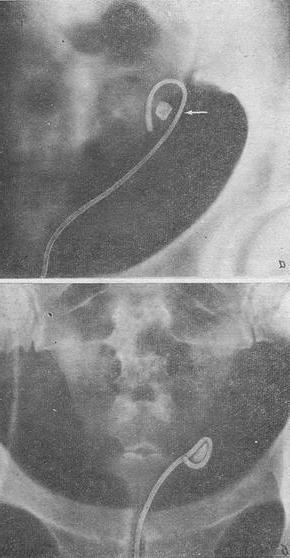

![]() Рис 9 Камінь сечоводу, захоплений петлею Цейса після эндовезикальной новокаїнової блокади: а - після першої блокади; б - після повторної блокади. |

Хороші результати, досягнуті при застосуванні комбінованих методів лікування, пояснюються тим, що у всіх випадках, коли пройти вище каменю не вдавалося, застосовувалася новокаїнова блокада гирла сечоводу з антибіотиками. Вже після 1-3 блокад нам вдавалося провести петлю вище каменю, захопити його і видалити (рис. 9, а, б).